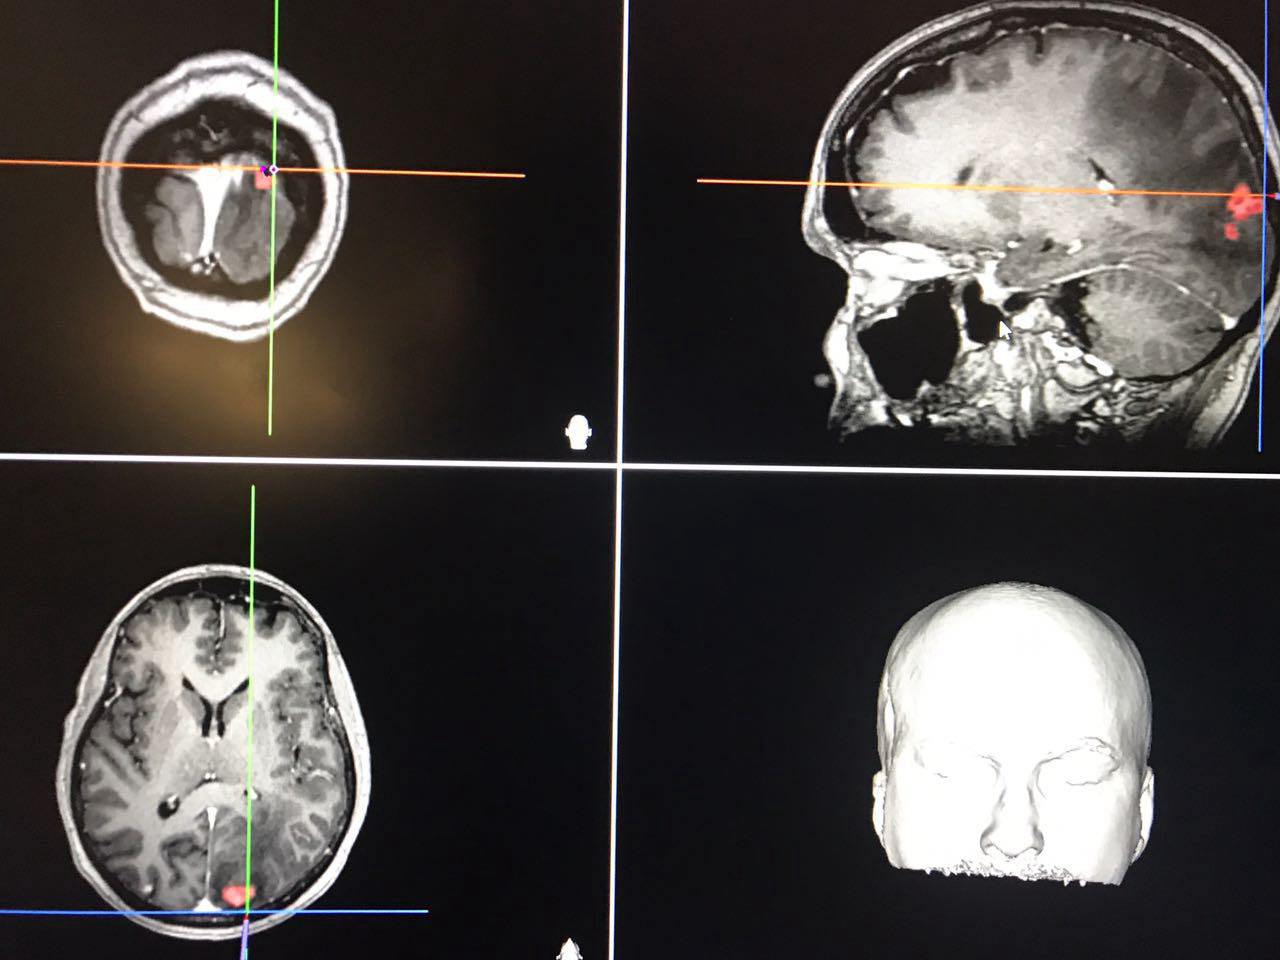

Minha paixão pelo cérebro e pela coluna vertebral floresceu no terceiro ano da faculdade, quando decidi abraçar a Neurocirurgia como especialidade. Durante minha formação, tive a honra de aprender com grandes mestres, que não apenas compartilharam conhecimento técnico, mas também ensinaram a importância da empatia e da valorização do ser humano.